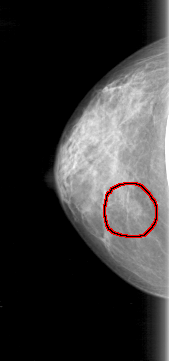

FILE: D_4085_1.RIGHT_MLO.OVERLAY

TOTAL_ABNORMALITIES 1

ABNORMALITY 1

LESION_TYPE MASS SHAPE OVAL MARGINS OBSCURED

ASSESSMENT 0

SUBTLETY 3

PATHOLOGY BENIGN

TOTAL_OUTLINES 1

BOUNDARY

RIGHT_MLO LINES 5101 PIXELS_PER_LINE 2131 BITS_PER_PIXEL 12 RESOLUTION 43.5 OVERLAY